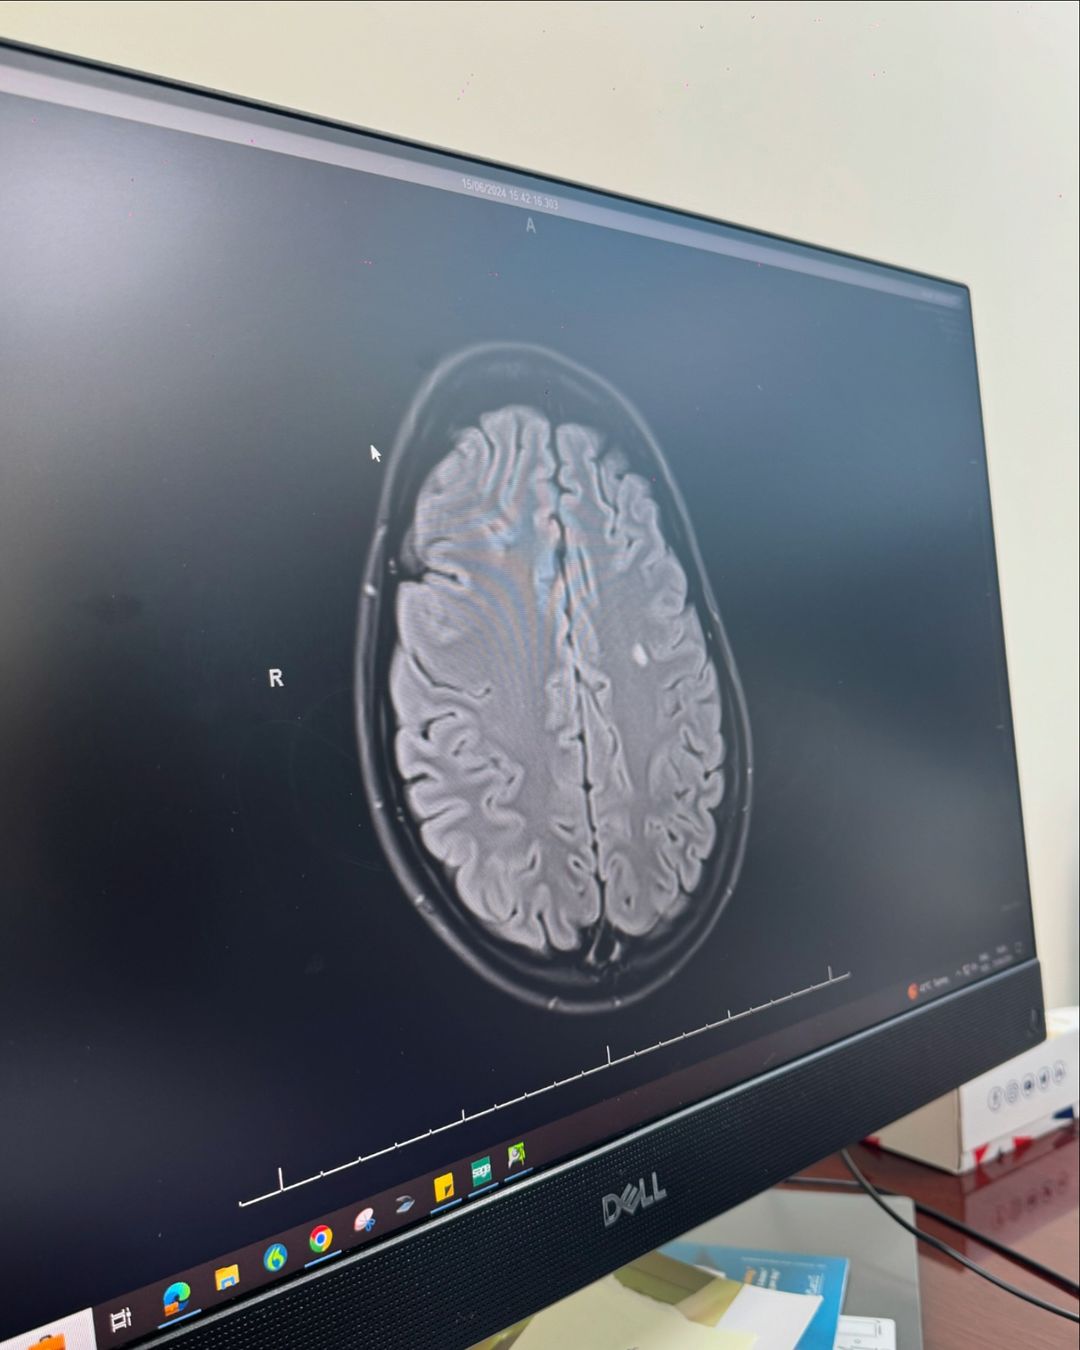

وتابعت:"من فترة تعبت صحتي و حسيت انه في شي غلط بجسمي ف رحت اعمل فحوصات عامة و ما كنا نعرف السبب للتعب الجسدي لبين ما قررنا نعمل رنين مغناطيسي للدماغ، و اكتشفنا انه كان في عندي ٣ نقط بيض على الدماغ بأحجام مختلفة و حاليا رح أخوض رحلة لمدة سنتين لحتا أتابع مع الدكتور لنتأكد انه ماله مرض مناعي و انشالله خير".